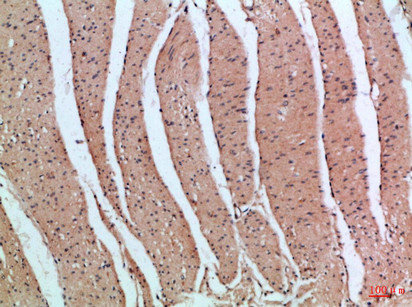

Immunohistochemical analysis of paraffin-embedded Human-colon, antibody was diluted at 1:100